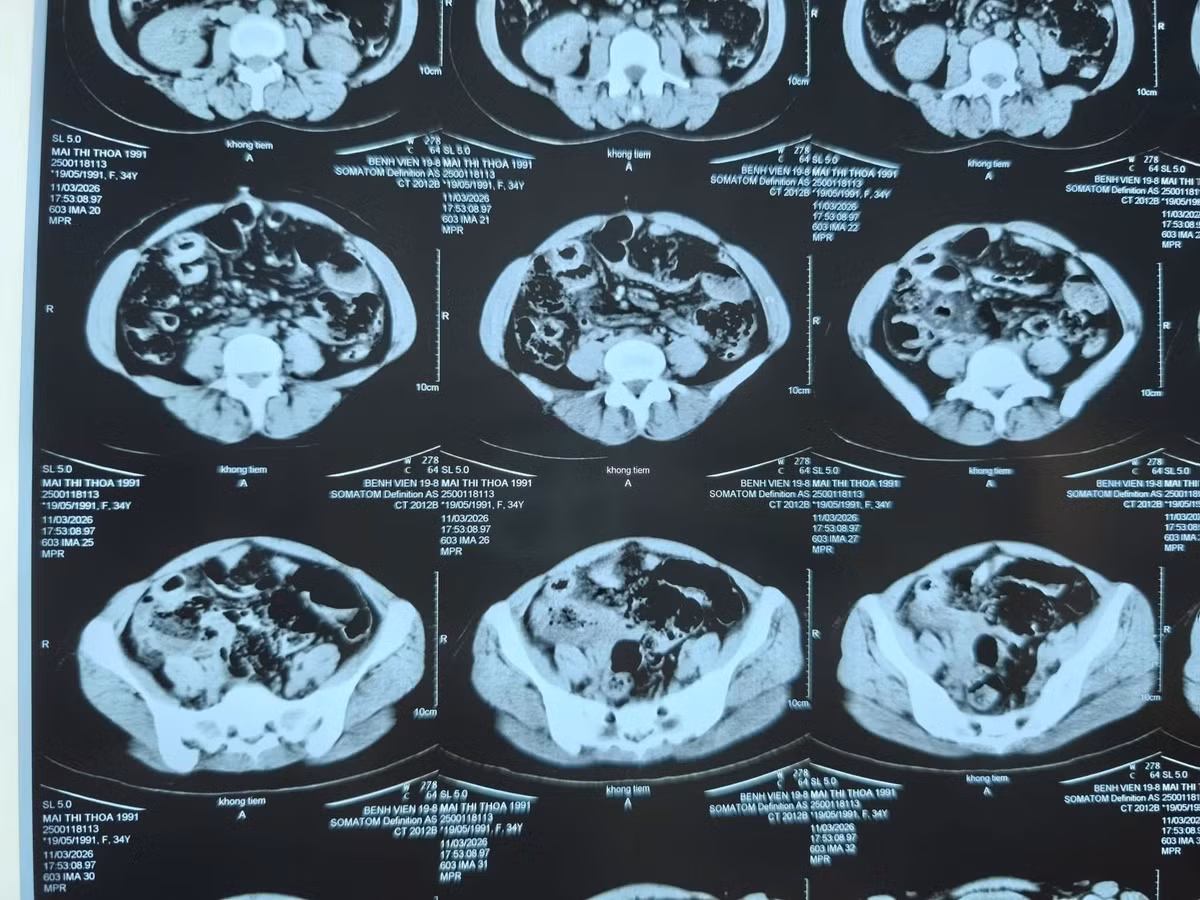

da-tui-thua1.jpg

Hình ảnh đa túi thừa trên phim chụp - Ảnh BVCC

Kết quả chẩn đoán ban đầu qua CT Scanner gây nhầm lẫn với tắc ruột do bã thức ăn. Đây là một "cái bẫy" hình ảnh học phổ biến vì túi thừa chứa phân non rất dễ bị nhầm với khối bã thức ăn.

Khi tiến hành phẫu thuật, ê-kíp bác sĩ đã ghi nhận tình trạng thực tế phức tạp hơn nhiều: Đoạn hỗng tràng dài 60cm chứa hàng chục túi thừa lớn (2-5cm) nằm san sát dọc bờ mạc treo. Một túi thừa đã bị áp xe hóa, gây viêm dính nặng nề và tắc ruột cơ học.